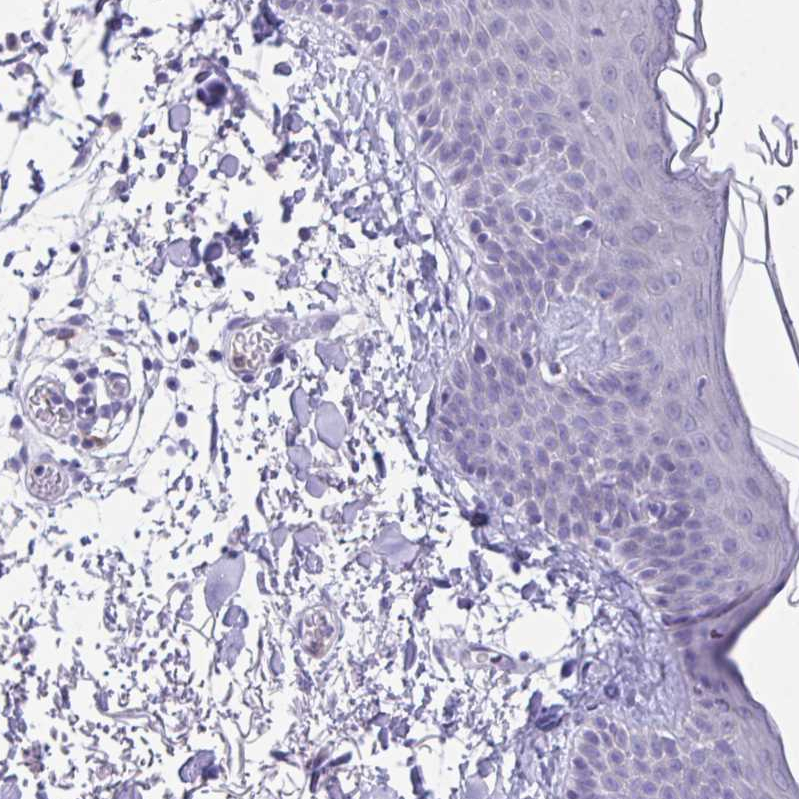

Immunohistochemical staining of human bone marrow shows moderate cytoplasmic positivity in hematopoietic cells.